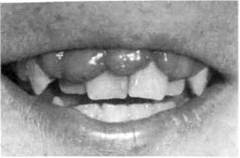

У детей, больных диабетом, рано появляются катаральный гингивит, который быстро переходит в пародонтит (характерный цианотичный цвет, пастозность и рыхлость десны, обильные, выбухающие из карманов грануляции). Экссудат может быть гнойным и геморрагическим. Постепенно развивается подвижность зубов. Глубина морфологических изменений в кости обычно соответствует тяжести гингивита (рис. 8.8). Наиболее характерный вид рассасывания костной ткани лунок — воронкообразная резорбция в области моляров. При тяжелой стадии заболевания подвижность зубов резко выражена и часто не соответствует степени деструкции костной ткани.

Рис. 8.8. Пародонтолиз при сахарном

диабете.